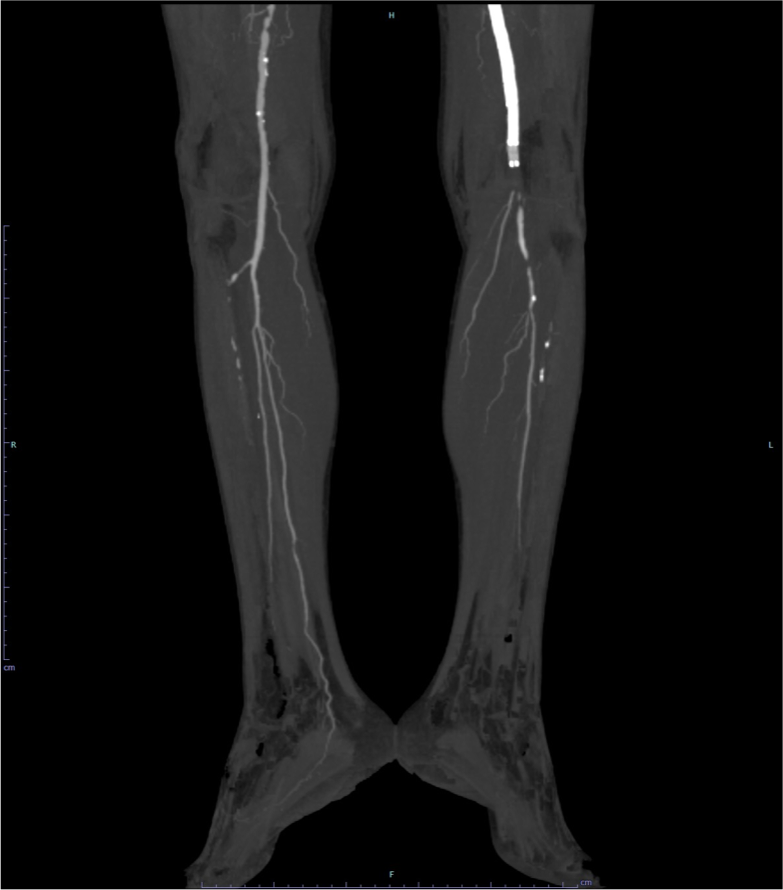

図2.下肢造影CT MIP像 (膝窩・膝下領域)

左SFA-Pop. Aステント遠位端より尾側とPop. A P3部に閉塞が認められる。左膝下領域の動脈描出が不良である